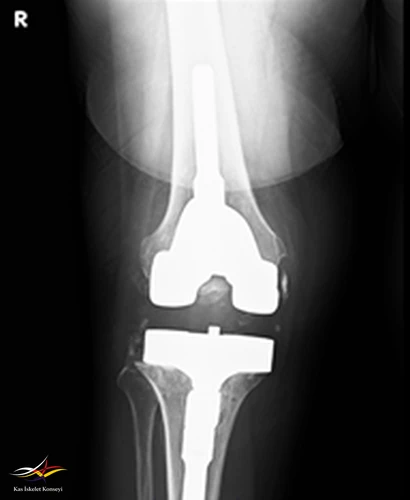

Resim 3. Revizyon ameliyatı sonrası AP direkt grafi.